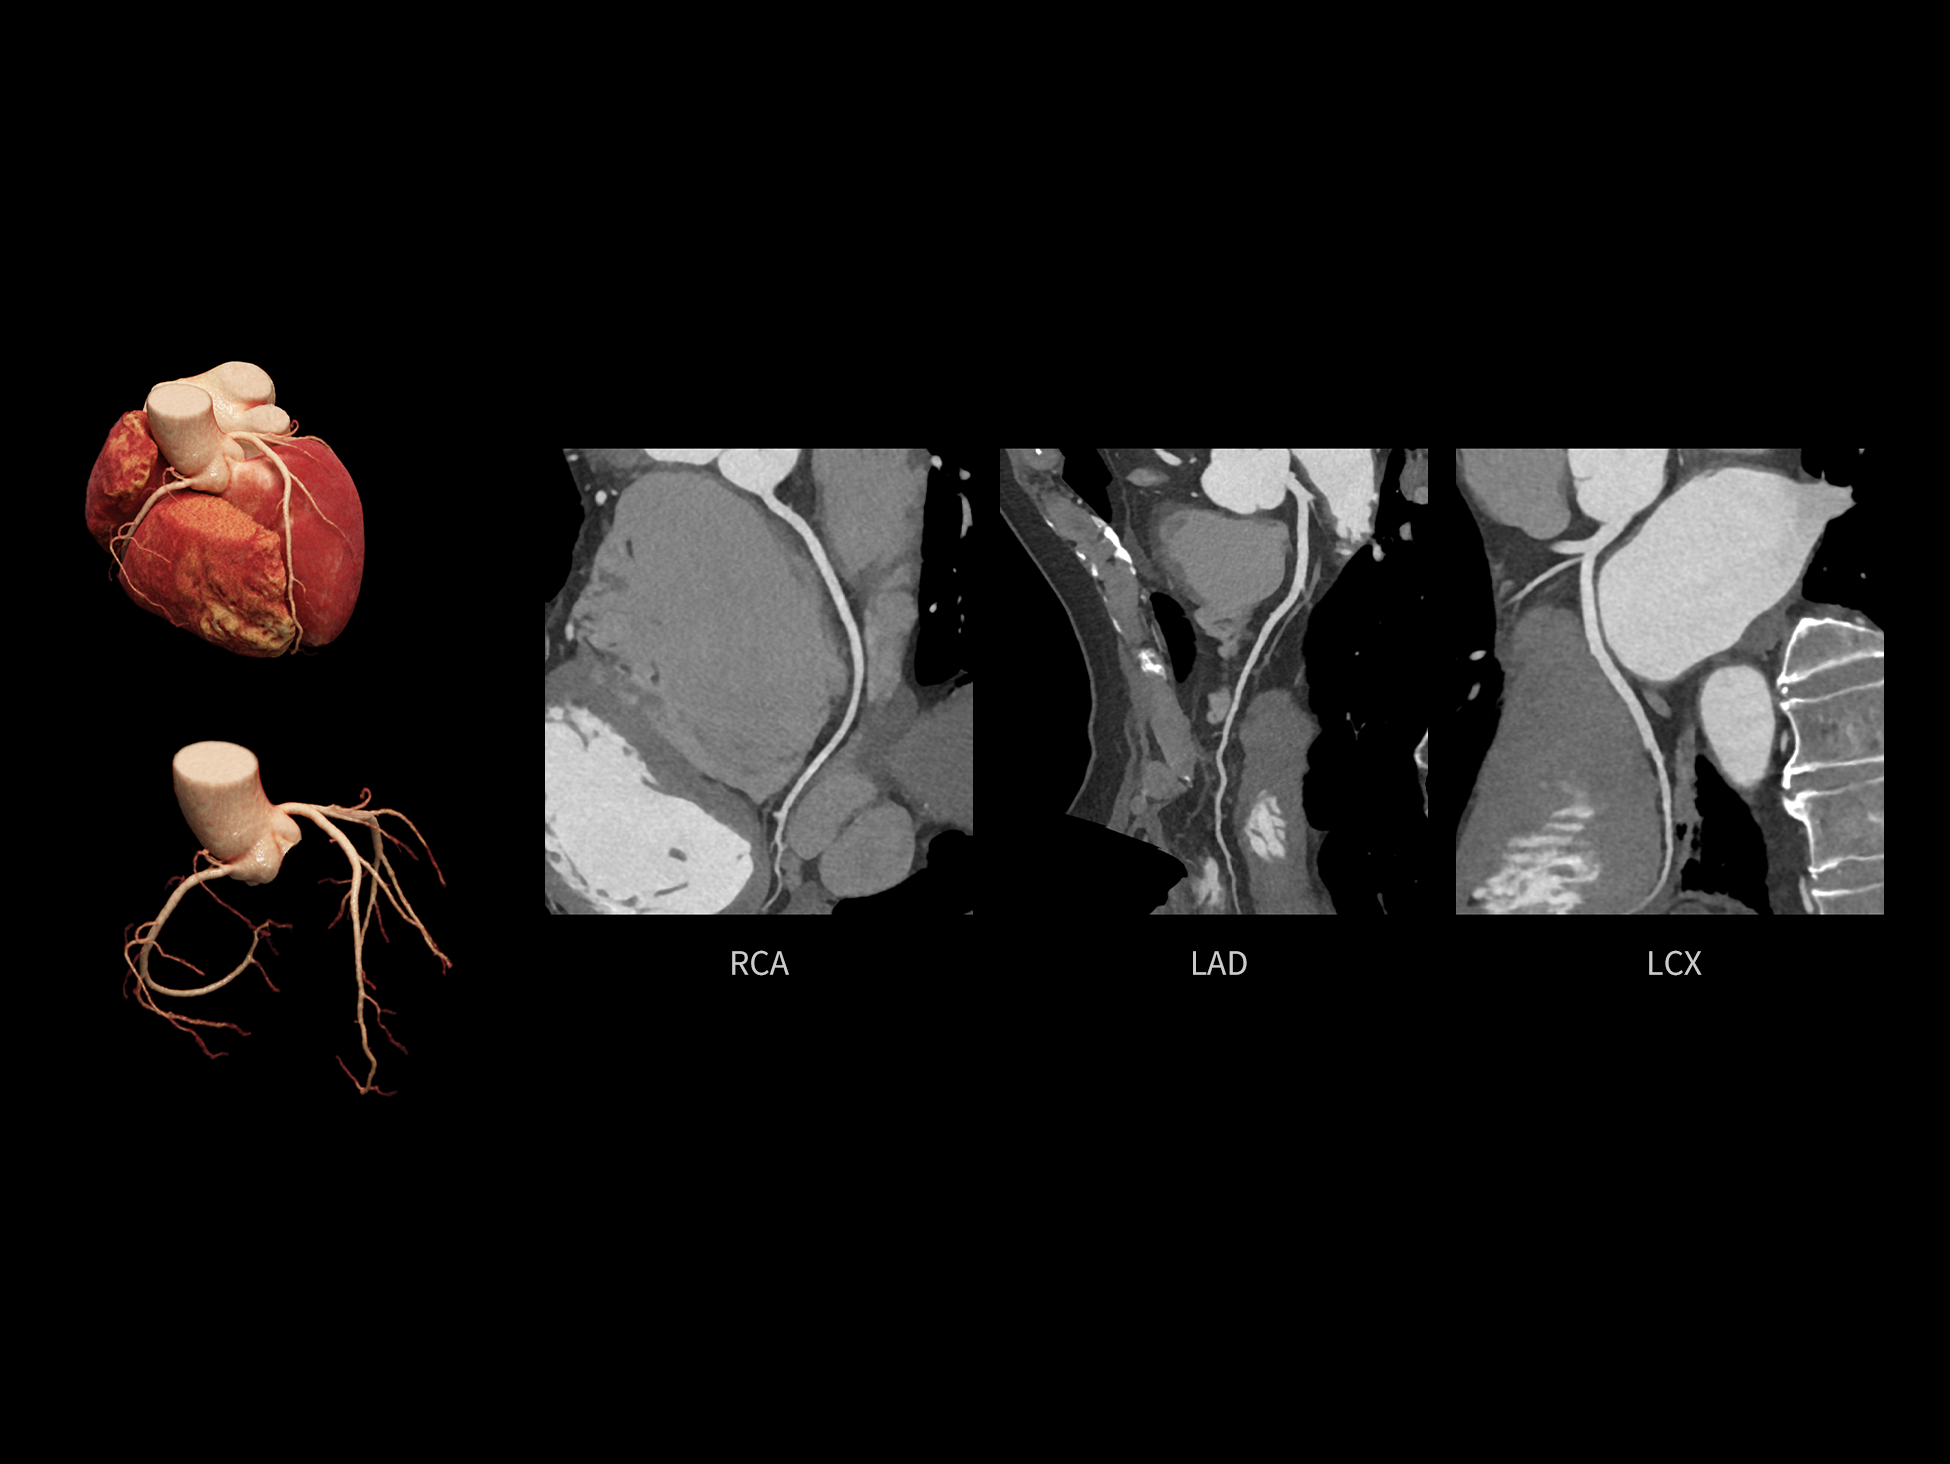

全时心脏

uCT SiriuX® 依托16cm超宽探测器与双源能谱技术,实现真正意义上的全身高清能谱成像。单次扫描同步获取灌注、能谱等多维定量参数,精准解析组织特性与病灶成分,为临床决策提供更深层次的诊断依据。

能谱成像可揭示丰富的物质与能量信息,其临床价值的充分释放有赖于完善高效的后处理分析平台。uCT SiriuX® 提供全面能谱高级分析工具,覆盖心血管、肿瘤、神经、骨科等多类临床场景。平台支持动脉增强分数分析(AEF)、细胞外容积分析(ECV)、肿瘤同源性分析、肺栓塞分析、骨髓水肿分析等多项评估,并提供多达10种基物质对成像,为精准诊断与科研探索提供坚实支撑。